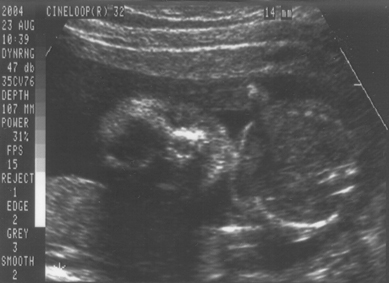

23. August 2004 (Ein Mädchen !)